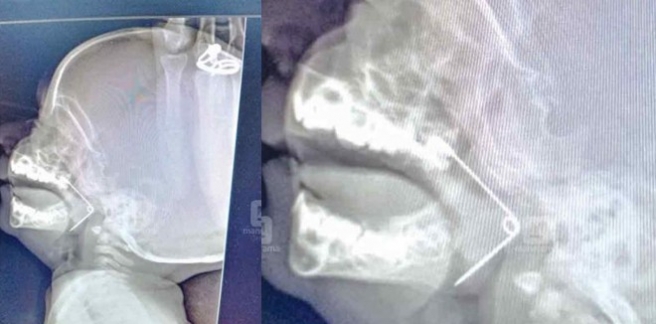

പിഞ്ചുകുഞ്ഞിന്റെ നിർത്താതെയുള്ള കരച്ചിൽ കേട്ട് പരിഭ്രാന്തരായി വീട്ടുക്കാർ. കുഞ്ഞുമായി സമീപത്തെ ആശുപത്രിയിൽ എത്തിയപ്പോൾ അറിഞ്ഞത് നടുക്കുന്ന വിവരം. പിഞ്ചുകുഞ്ഞിന്റെ തൊണ്ടയിൽ സേഫ്റ്റി പിൻ കുടുങ്ങുകയായിരുന്നു. അപൂർവ ശസ്ത്രക്രിയയിലൂടെ ഇത് പുറത്തെടുക്കുകയുണ്ടായി .

കരുനാഗപ്പള്ളി കെഎസ് പുരം സ്വദേശികളായ ശിഹാബുദ്ദീൻ സുലേഖ ദമ്പതികളുടെ മകൻ മുഹമ്മദ് ഇസിന്റെ തൊണ്ടയിൽ ആണ് പിൻ കുടുങ്ങിയത്. കുഞ്ഞിന് 10 മാസം മാത്രമേ പ്രായമായിട്ടുള്ളൂ. കൊല്ലം ട്രാവൻകൂർ മെഡിസിറ്റി ആശുപത്രിയിൽ നടന്ന ശസ്ത്രക്രിയയിലാണ് പിൻ പുറത്തെടുത്തത്.

അനസ്തേഷ്യ നടത്തി ലാറിംഗോസ്കോപ്പിയിലൂടെ പിൻ പുറത്തെടുക്കുകയായിരുന്നു. പിന്നിന്റെ മുകൾ ഭാഗം മുക്കിന്റെ പിന്നിലേക്കും കൂർത്ത ഭാഗം ശ്വാസനാളത്തിന്റെ മുകളിലും തറച്ചിരുന്നു. അതുക്കൊണ്ടായിരുന്നു വായ അടയ്ക്കാൻ കഴിയാതിരുന്നതെന്നു ഡോക്ടർമാർ വ്യക്തമാക്കി .